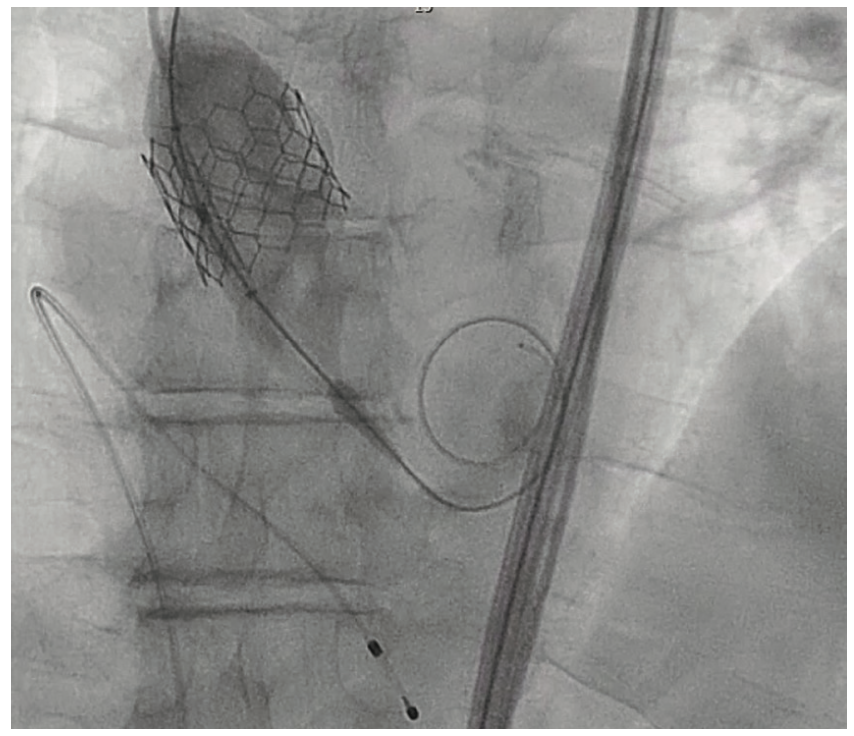

During the TAVR procedure, a Sapien 3 26 mm valve was loaded over a Safari wire (Boston Scientific) and advanced into the aortic annulus under fluoroscopy, with good planar angle positioning confirmed using contrast injection. After valve placement, rapid ventricular pacing was performed and the valve was deployed. However, immediately following deployment, the valve embolized into the ascending aorta. The valve was carefully pulled distally and secured just proximal to the origin of the right brachiocephalic artery. It was dilated with an extra 4 mL volume with two inflations performed. To confirm the patency of the right subclavian artery and the right brachiocephalic artery, access was subsequently obtained in the right radial artery, and no difference in the arterial pressure was noted as the catheter was advanced from the right radial artery into the aortic root. A second Sapien 3 26 mm valve was then loaded over the Safari wire and was similarly advanced into the aortic annulus under fluoroscopy, with good coplanar angle positioning confirmation via contrast injection. After rapid ventricular pacing, the second valve was deployed without issue. A post procedure aortogram confirmed good valve positioning, the absence of significant paravalvular leak, and patency of the left coronary artery. A limited echocardiogram also confirmed good valve positioning, the absence of paravalvular leak, and the absence of pericardial effusion. The patient tolerated the procedure well and left the cardiac catheterization laboratory in a stable condition. After chest x-ray confirmed stable positioning of the embolized valve in the ascending aorta, the patient was discharged on postoperative day one with a scheduled follow-up visit in three weeks.